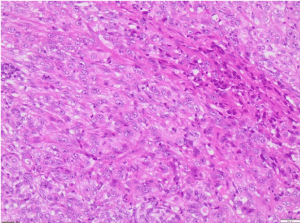

Histological features and immunoprofile of metastatic high grade sarcomatous renal carcinoma of left supraclavicular lymph node were depicted in Figures 4-11.

Figure 4. H&E X100 (Haematoxylin and Eosin stain X100) shows poorly differentiated malignant tumour with no obvious squamous or glandular differentiation